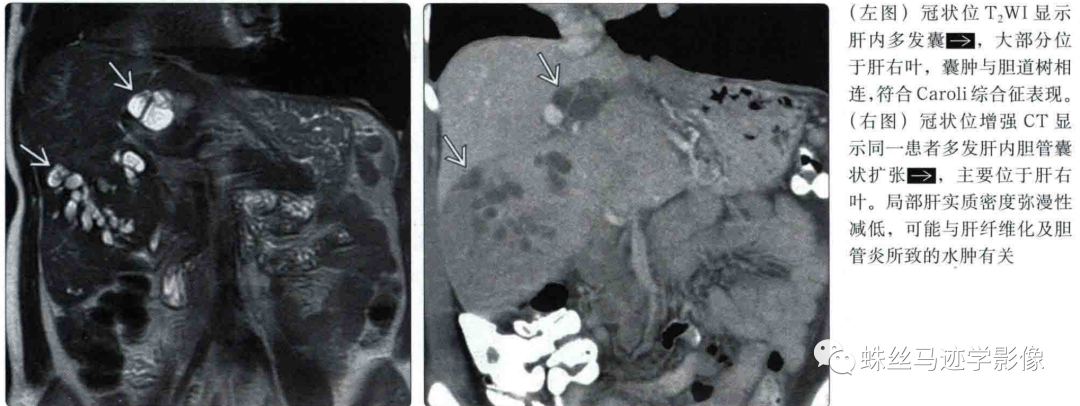

二、Caroli’s病(先天性肝内胆管囊状扩张症):